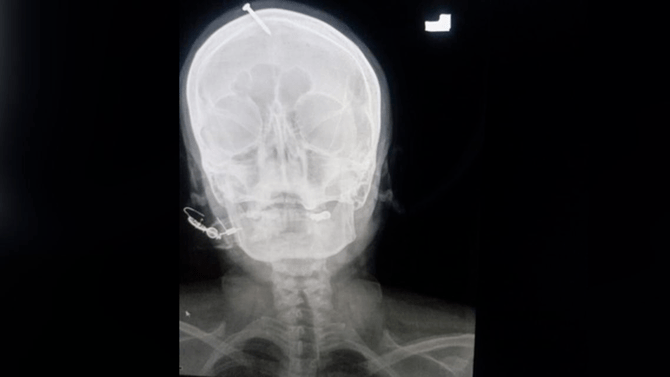

An X-ray showed the five-centimeter (two-inch) nail had pierced the top of the woman’s forehead but missed her brain.

An X-ray showed the five-centimeter (two-inch) nail had pierced the top of the woman’s forehead but missed her brain. (Twitter)